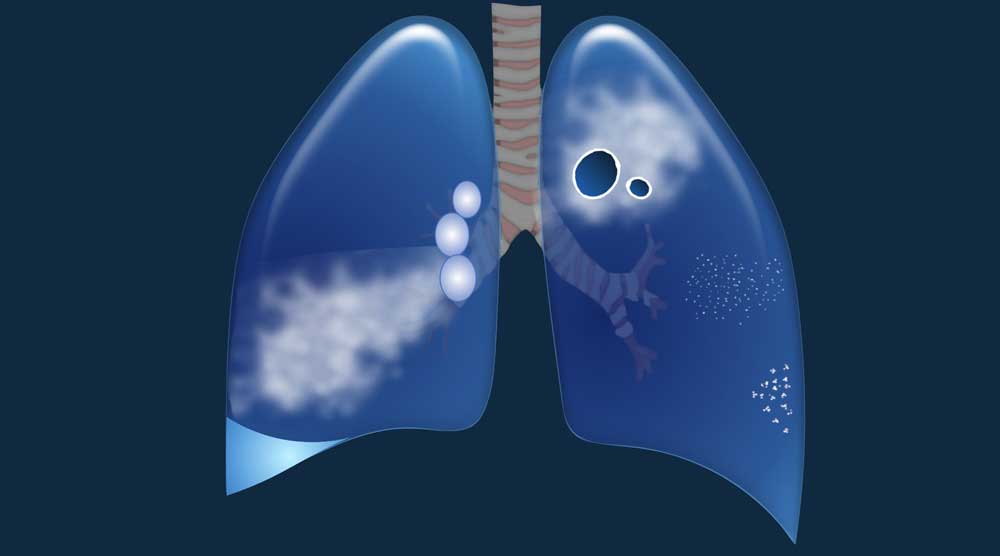

Cystic Lung Disease - Differential diagnosis